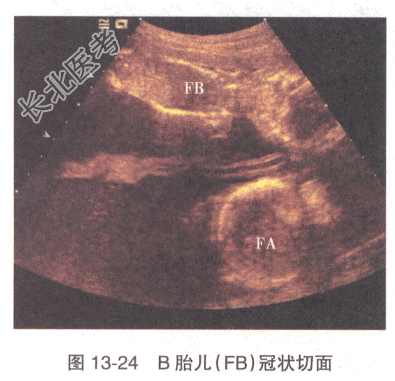

患者,女性,31岁。孕2产0,孕22周,感觉腹胀1周。无阴道流血及流水史。孕12周时超声检查示宫内妊娠,单绒毛膜囊双羊膜囊双活胎,A胎儿NT0.32cm,B胎儿NT0.12cm。22周超声检查,双胎儿解剖结构均未见明显异常,其余超声见图13-24~图13-27。

B、B胎儿为受血儿,羊水过少,贴附子宫前壁

E、B胎儿为供血儿,羊水过少,贴附子宫前壁